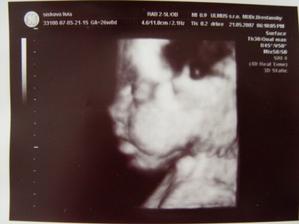

31.08.07 12:18 sa nám narodilo to najkrajšie dievčatko na svete Sofia,narástla nám 51 cm a vážila 3150 g.

Mamičku potrápila 2 dni ale vďaka ockovi ,ktorý bol nepretržite pri nás sme to zvládli.